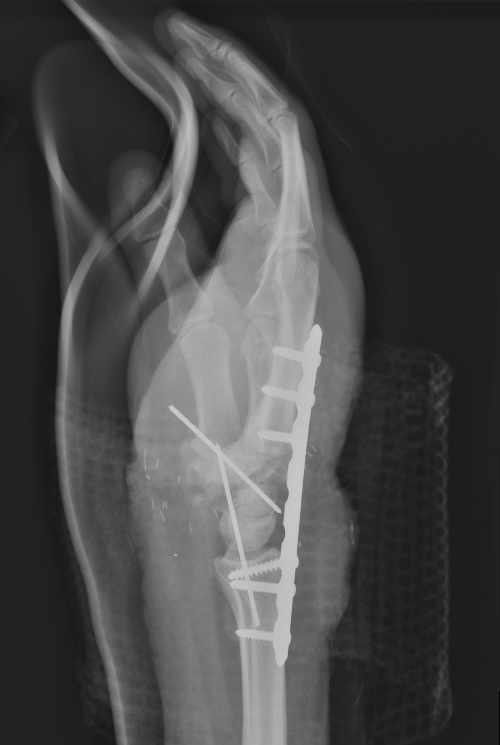

Technique

Rapid skeletal stabilisation

- at least one artery must be revascularised

- then follow sequence for digit

- extensive fasciotomies always indicated

- any exposed vessels must be covered by rotation flap etc

Ramji et al Plast Reconstr Surg Global Open 2020

- systematic review of 13 studies with 136 major limb replantation

- functional outcome related to level

- good to excellent outcome scores distal to elbow

- poor outcomes at or proximal to elbow